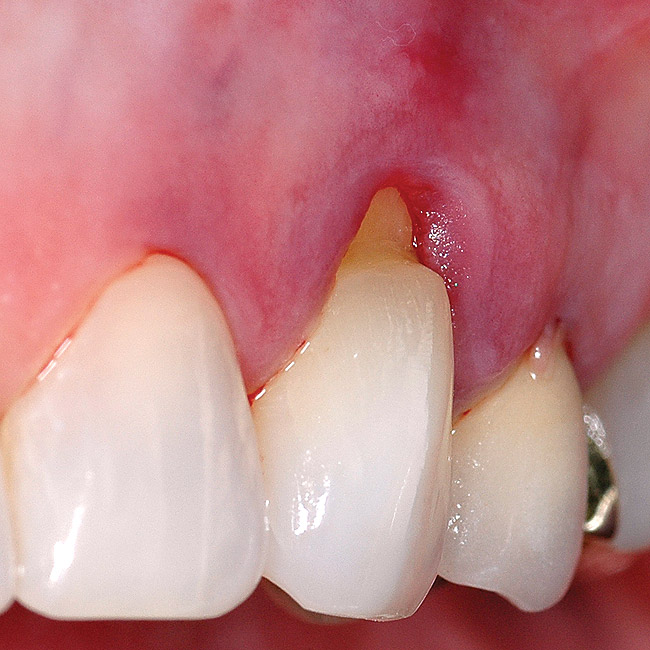

Fig 8 and Fig 9. Non-carious cervical lesions of moderate depth, Miller Class III gingival recession, absence of attached gingiva, shallow vestibule, and extrusion of the central incisors.

Figure 8

Figure 9